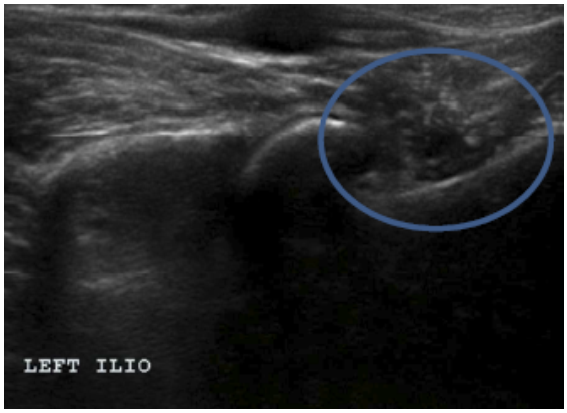

Methods: Medical records of 73 agility performance canines that underwent musculoskeletal ultrasound evaluation of bilateral iliopsoas muscle groups were retrospectively reviewed. Data included signalment, previous radiographic findings, and ultrasound findings. A 3-tier grading scheme for acute strains was used while the practitioner also evaluated for evidence of chronic injury and bursitis.

Results: The majority of pathologies were localised to the tendon of insertion, with the majority being low grade I-II strains (80.8%). Tendon fibre disruption (71.2%) and indistinct hypoechoic lesions (91.8%) were the most common of acute changes noted. Hyperechoic chronic changes were noted in 84.9 percent of cases. Acute and chronic changes were commonly seen together (62.8%).

Conclusion: Diagnostic musculoskeletal ultrasound was used to identify lesions of the iliopsoas tendon consistent with acute and chronic injury, as well as identifying the region of pathology. The majority of agility performance dogs had low grade acute strains based on the tiered system, with mixed acute and chronic lesions being noted frequently.

Application: Diagnostic musculoskeletal ultrasound provides a non-invasive diagnostic modality for patients suspected of having an iliopsoas strain.